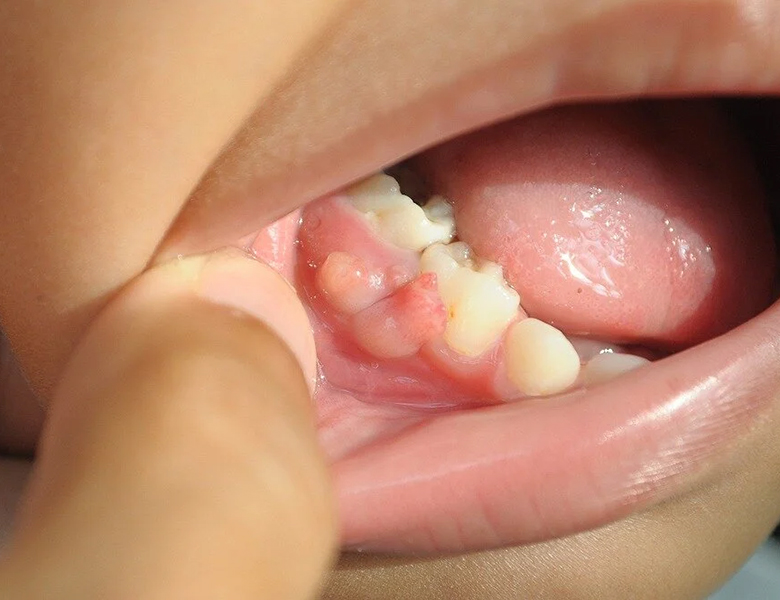

手足口病・ヘルパンギーナ

主に夏風邪の一種として、喉の奥や口の中に多数の小さな水ぶくれや潰瘍ができます。

お子さまに多いですが、大人が感染すると重症化することもあります。